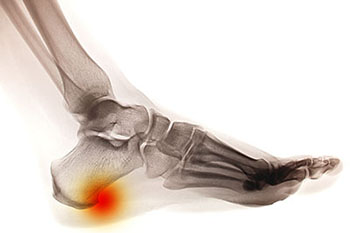

Heel Spurs

heel spur

Heel spurs are brought upon by a calcium deposit that causes a bony protrusion on the underside of the heel bone. It normally forms over time and can best be diagnosed through an x-ray examination. Heel spurs are commonly linked with plantar fasciitis, an inflammation that runs along the bottom of the foot. Common symptoms of heel spurs include pain towards the affected area, inflammation, and swelling at the front of the heel.